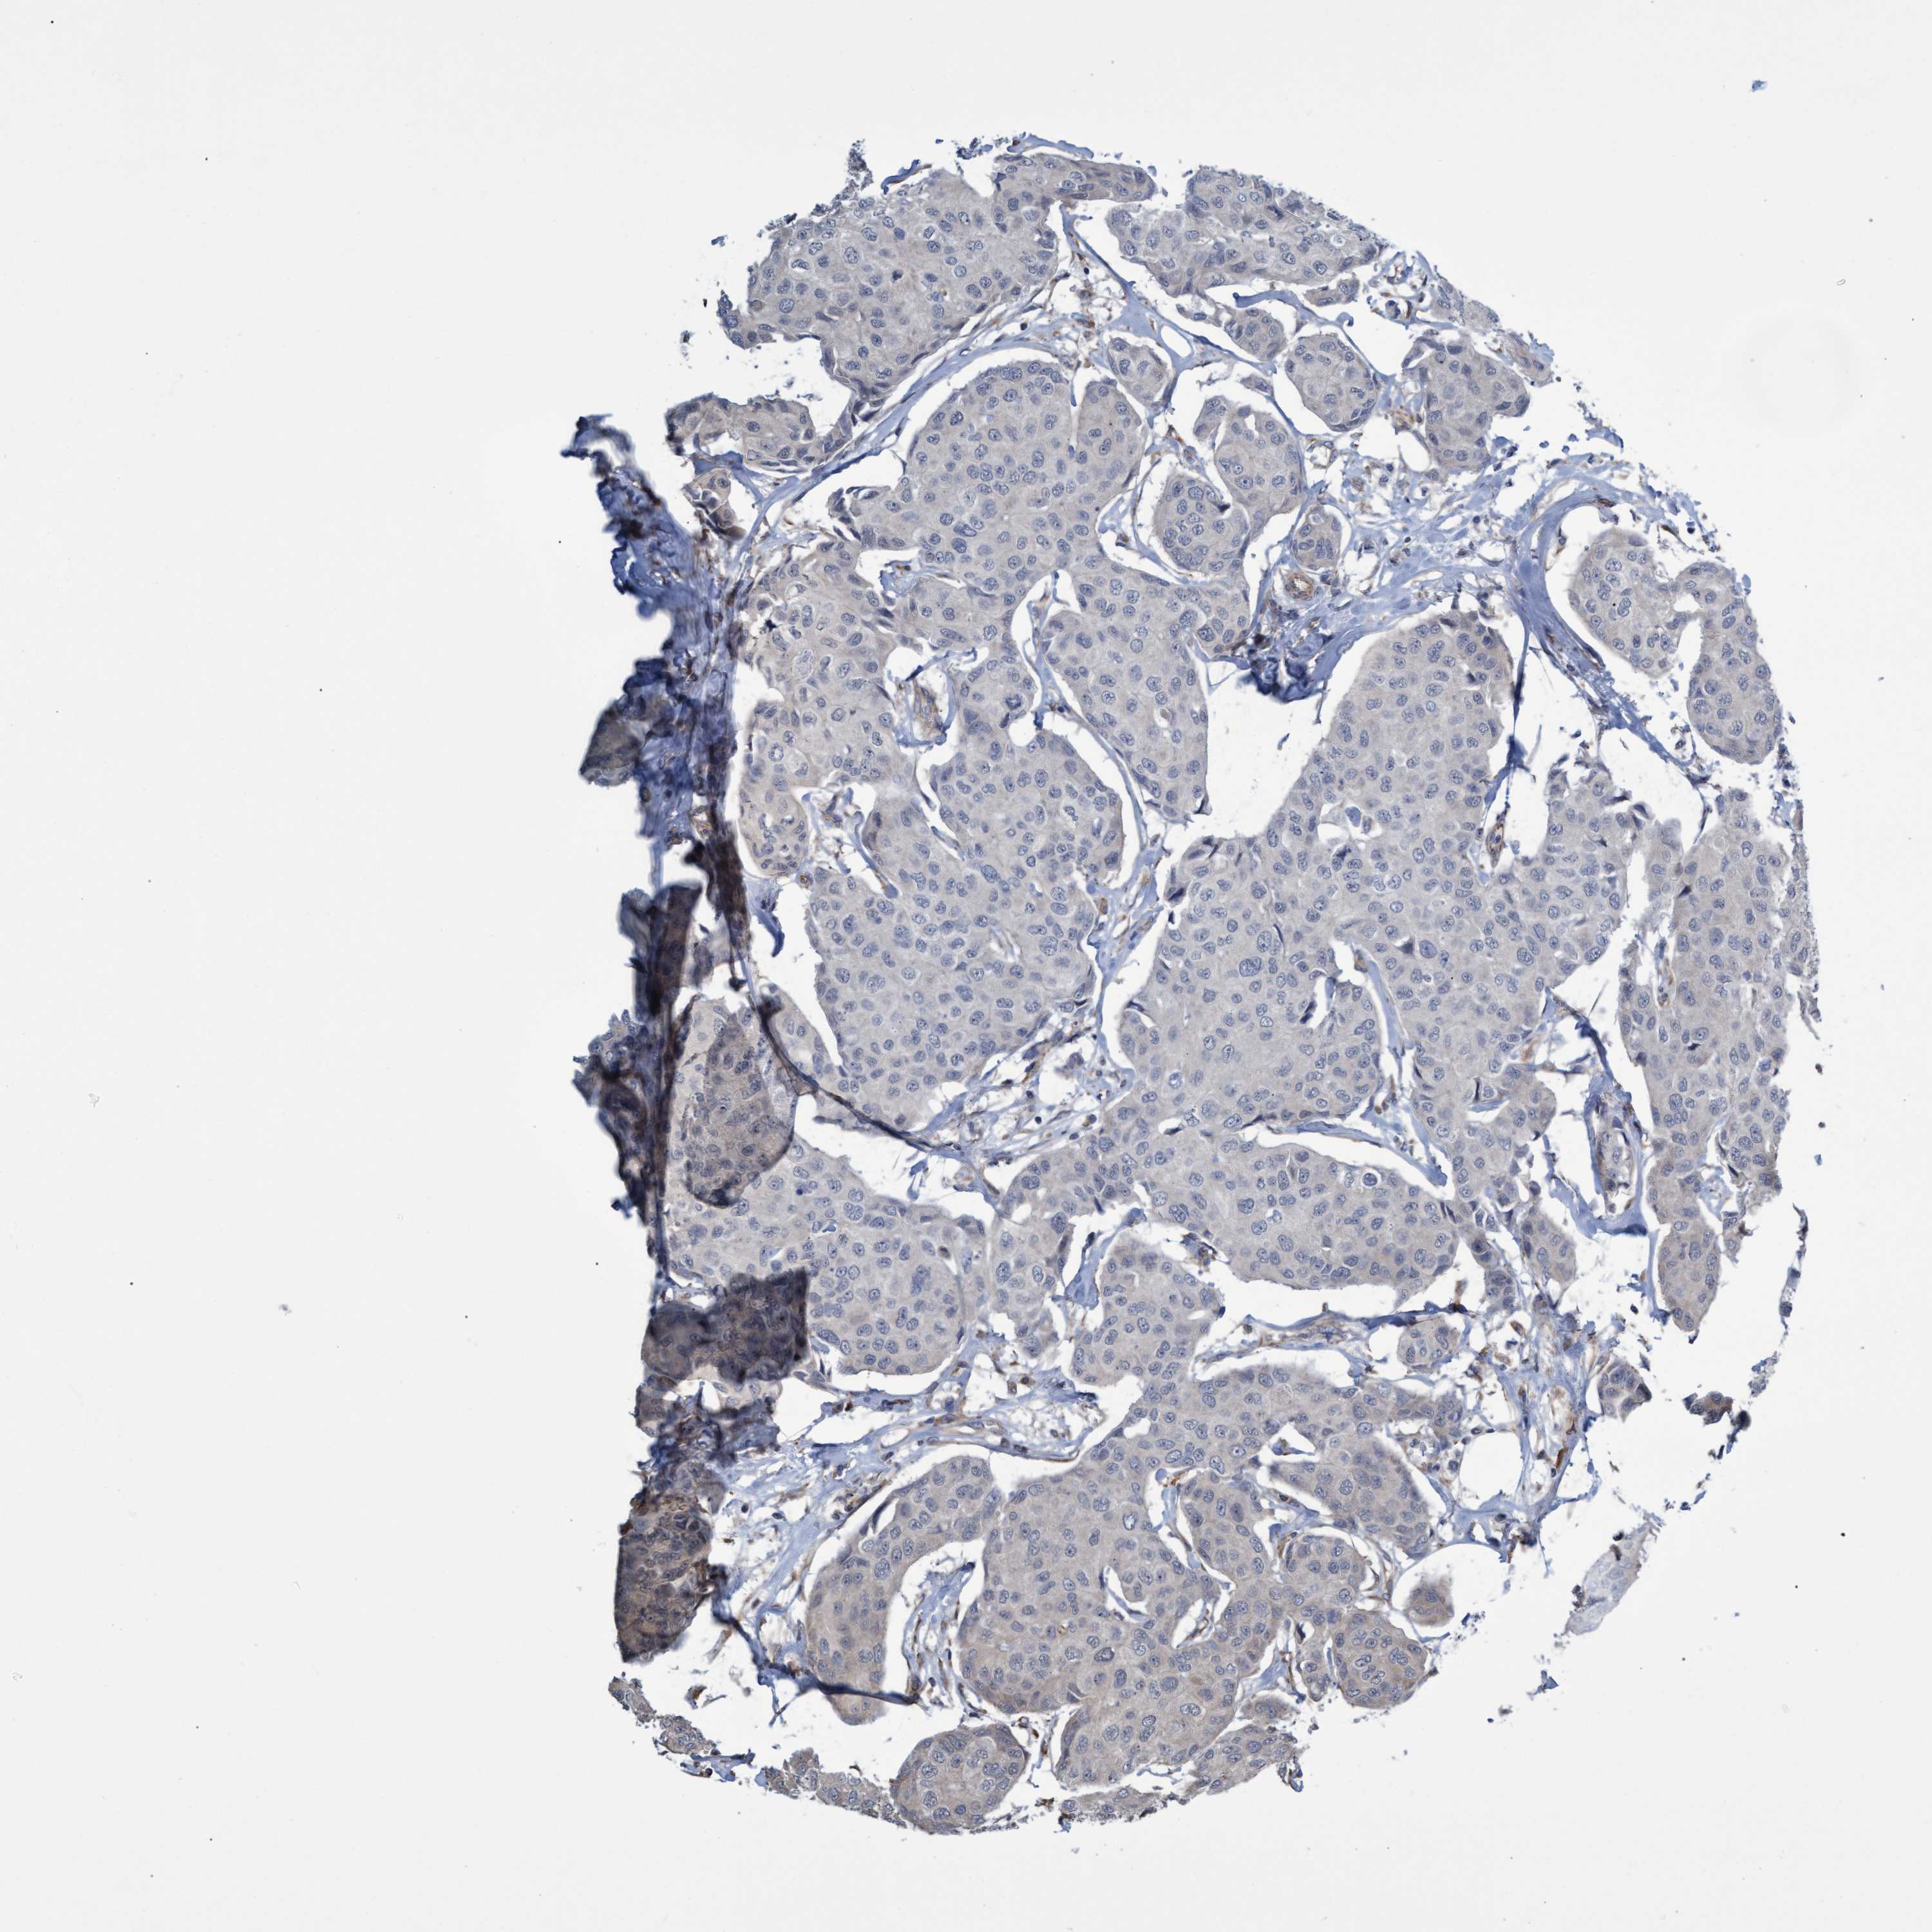

BRCA TCGA BRCA VALIDATION PROTEIN EXPRESSION